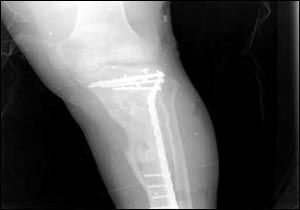

烏代傷腿的X光照片

7月24日,美國國防部通過由美國資助的伊拉克電視臺、兩家阿拉伯衛星電視臺以及美國本土的CNN(有線新聞網絡)將薩達姆的兩個兒子烏代和庫賽遭美軍擊斃慘死的照片公諸于世,同時被曝光的還有1996年烏代遇刺后所拍的傷腿的X光片。據悉,近60的伊拉克人收看這檔節目。此前,美軍中央司令部的里卡多·桑切斯中將在巴格達舉行新聞發布會時說,判斷烏代和庫賽被打死的依據是在現場發現的牙齒以及曾任薩達姆助手的目擊證人的指認。